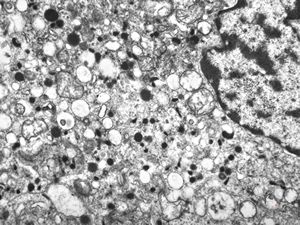

M, 62y. | pheochromocytoma